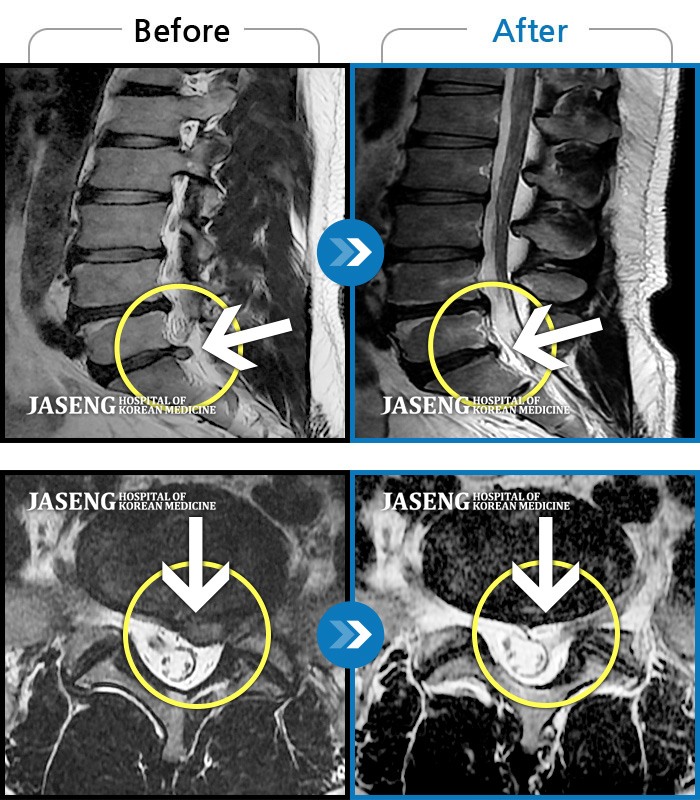

Before

After

환자에게 사전 동의를 받아 동일 조건에서 촬영되었습니다.

개인에 따라 치료 후 부작용이 발생할 수 있으니 의료진과 상담 후 치료를 진행하시기 바랍니다.

극심한 통증으로 허리를 조금도 움직이기 힘들었고, 오른쪽 허벅지 전면부 찌릿한 통증

2023.12월경에 눈길에 걷다가 삐끗한 후 발생한 허리 통증으로 오신 분입니다.